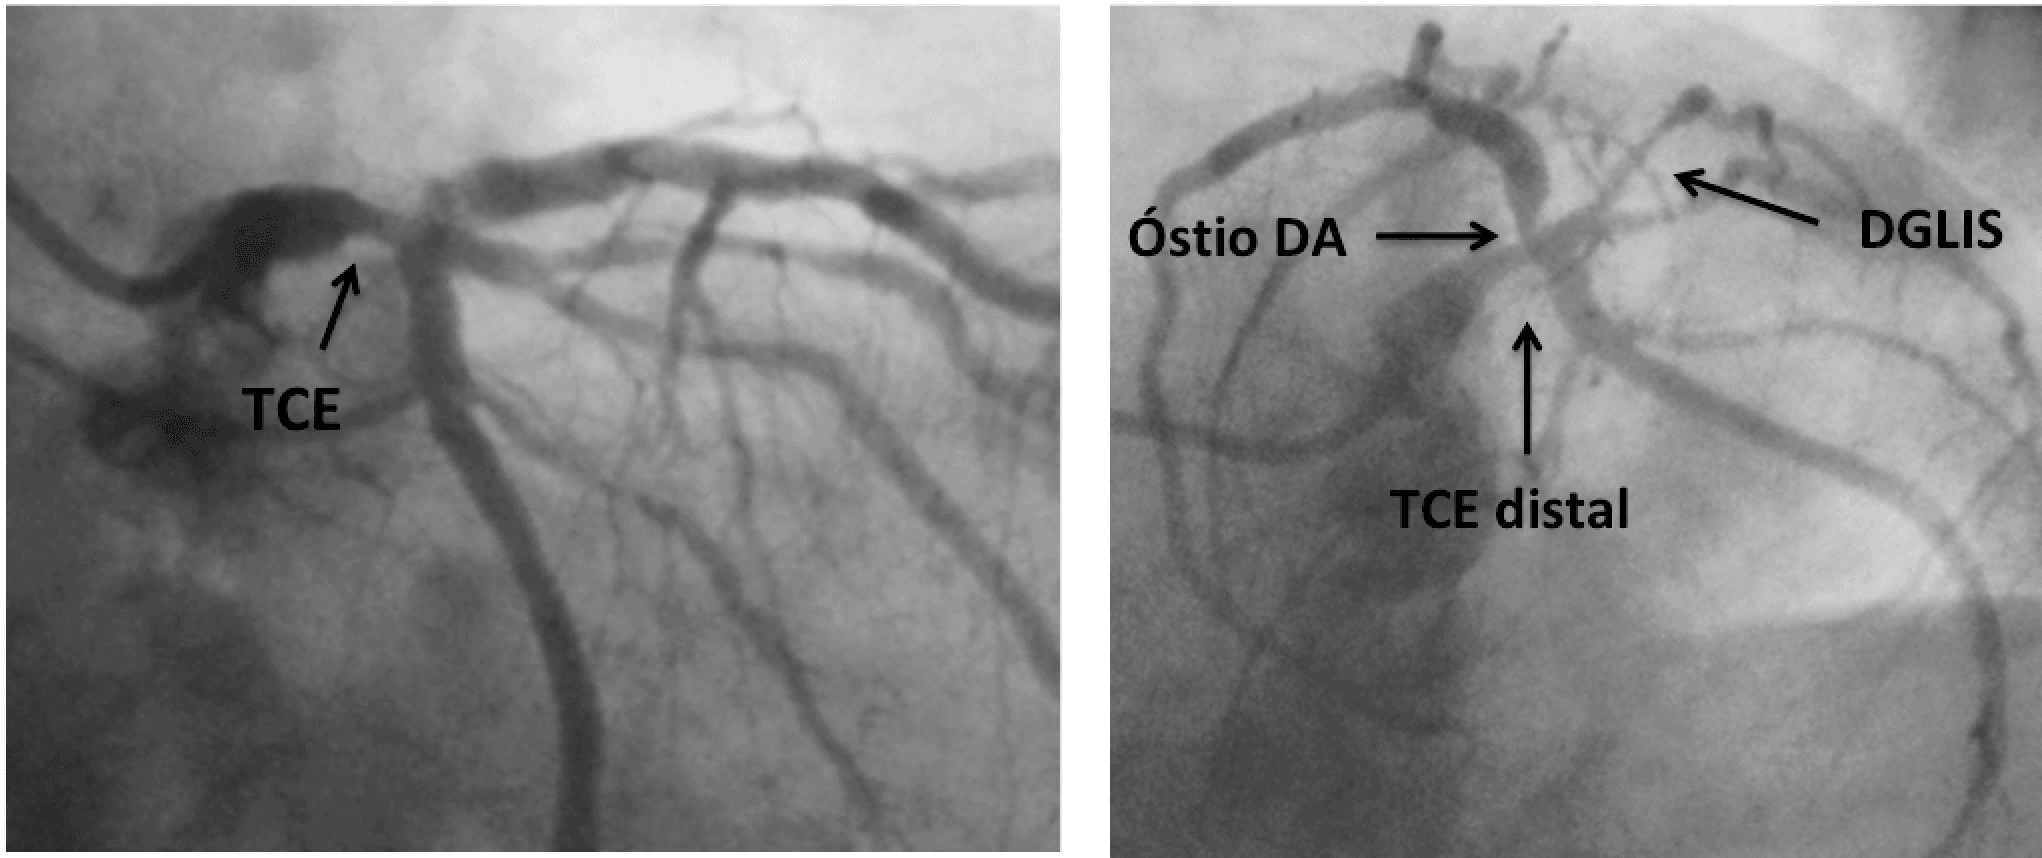

A detecção da doença arterial coronariana (DAC) é o passo inicial para o manejo de pacientes com coronariopatia crônica. Essa informação tem uma maior importância quando o tronco da coronária esquerda…

A angiotomografia de coronárias (ATC) mostrou grandes avanços tecnológicos nas últimas 2 décadas. Nos dias atuais, pacientes com suspeita de DAC obstrutiva com baixo/intermediário risco cardiovascular…